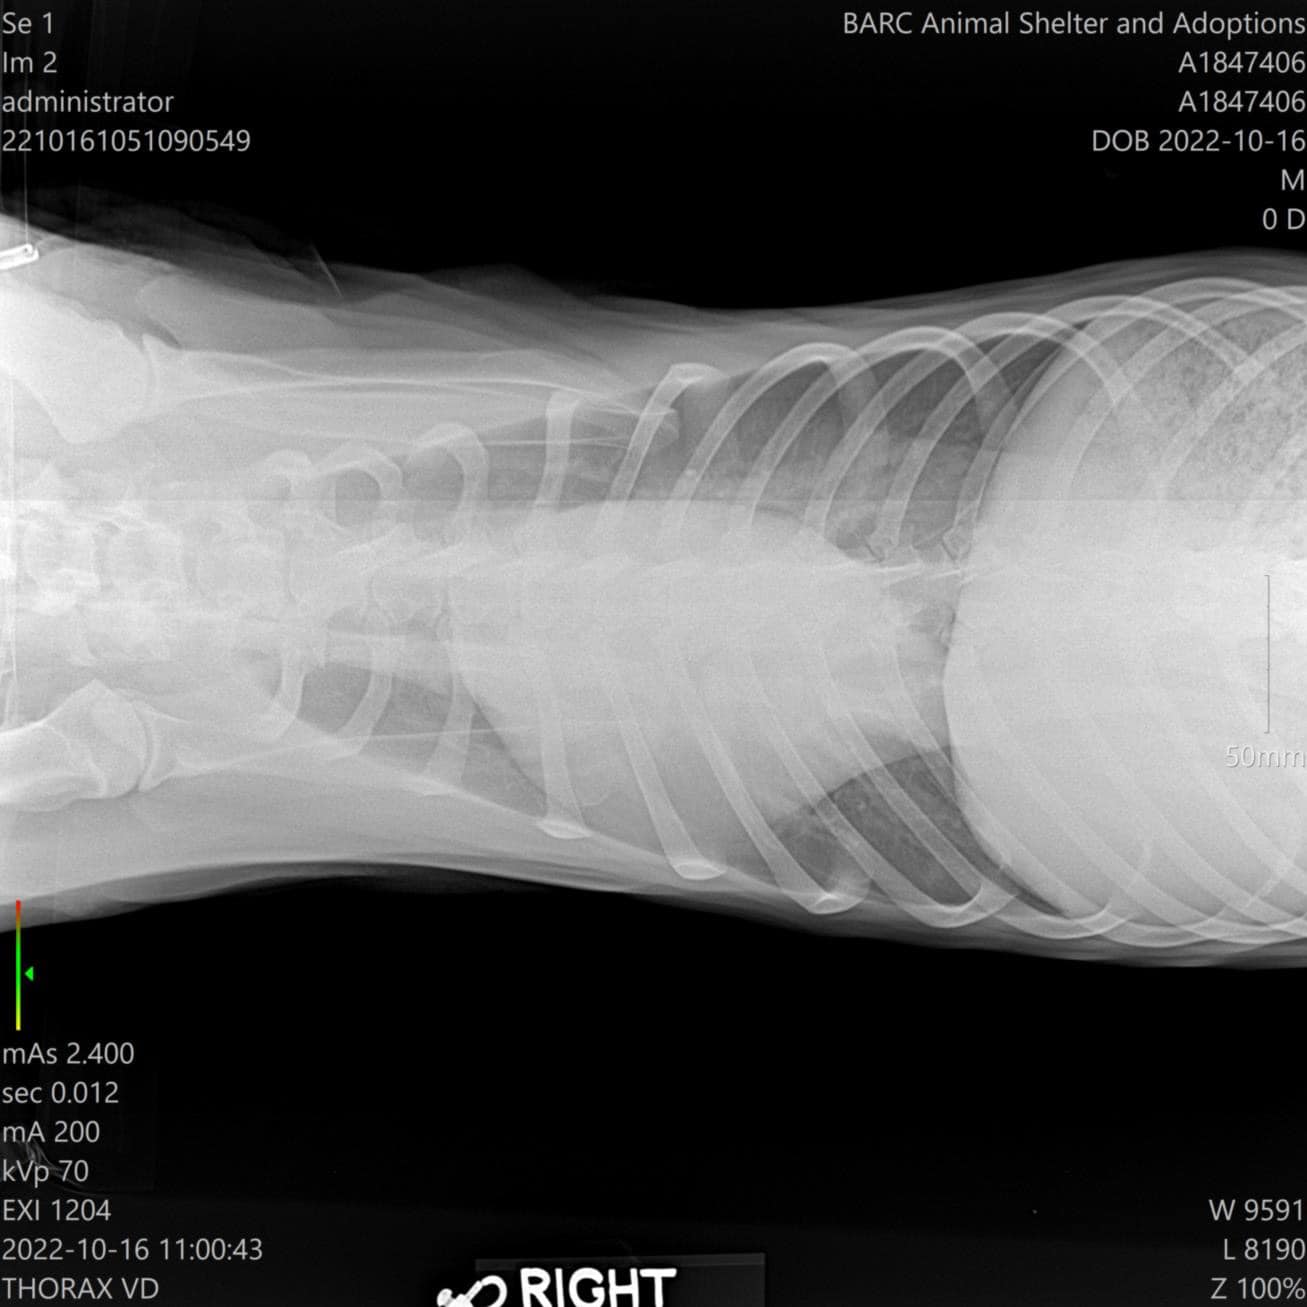

Sadly, X-rays revealed that Jerry has an enlarged heart due to untreated heartworm disease. Doctors said that his prognosis is poor and treatment is limited. He's currently staying overnight at the veterinarian for assessment and we will have more information tomorrow.